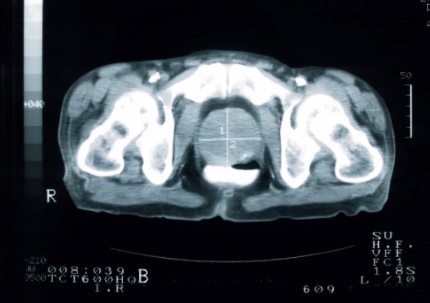

mpMRI Often Underestimates Prostate Tumour Size

The size of prostate tumours as indicated by multiparmetric MRI are often seen to be larger after surgery than the MRI indicated.

A team led by Aydin Pooli, MD, of the Institute of Urologic Oncology at the University of California, Los Angeles, published their results in the Journal of Urology and they showed that mean radiologic tumour size was significantly smaller than pathologic tumour size.

“Our study suggests that when considering management options for [prostate cancer], greater caution must be applied for smaller tumours on mpMRI and lower PI-RADSv2 scores given more significant size underestimation for such tumours,” Dr Pooli’s team stated. They highlighted the need for additional tools to determine tumour treatment margins when considering focal ablation therapies. Read more by clicking on the link:

Report: Multiparametric MRI Frequently Underestimates Prostate Tumor Size – Renal and Urology News

Source article: Pooli A, Johnson DC, Shirk J, et al. Predicting pathological tumor size in prostate cancer based on multiparametric prostate magnetic resonance imaging and preoperative findings. J Urol. 2021:205:444-451. doi:10.1097/JU.0000000000001389